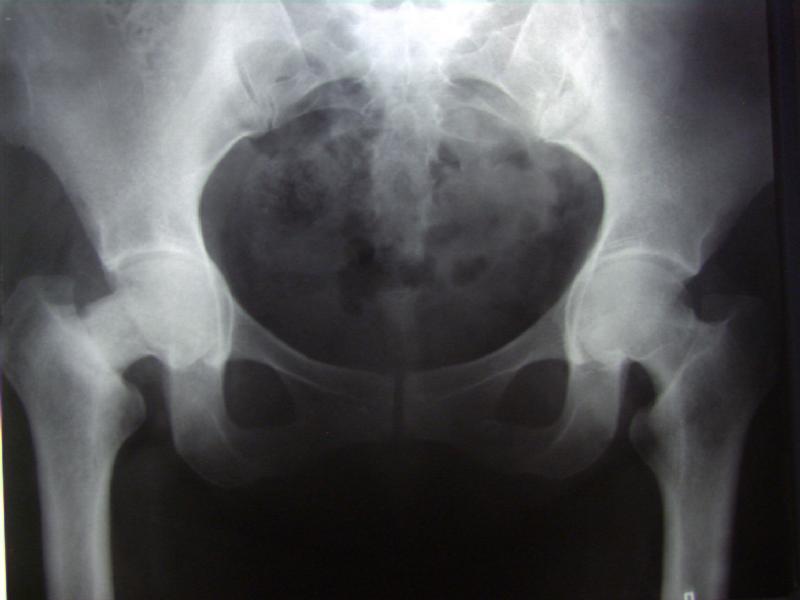

Женщина лет 40 переведена к нам из городской больницы с переломом шейки бедра.

Упала дома 5.11.02. С ее слов, в послдений год лечилась консервативно от якобы коксартроза с этой же стороны. Снимков не делали. Этот сустав болит последние несколько месяцев. На снимках обращает на себя "замыленность" краев. Не усталостный ли это перелом? Дама полноватая. Ограничения амплитуды движений до травмы она не отмечала.Мнения о тактике у нас разошлись в диапазоне от остеосинтеза винтами до эндопротезирования, с остеотомиями между ними. Помогите, пожалуйста, обосновать выбор.

Прилагаю еще одну рентгенограмму - обзорный снимок таза от 11 ноября, еще до перевода к нам. Ранее были посланы снимки, сделанные 13 ноября

уже у нас.